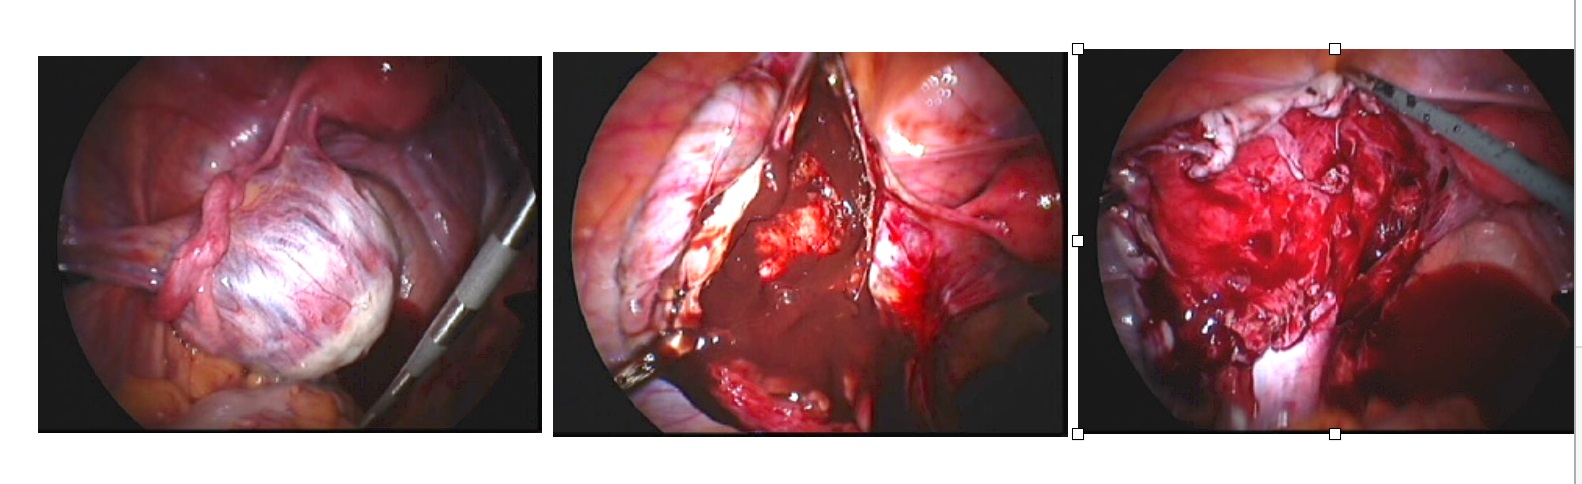

Endometriosis